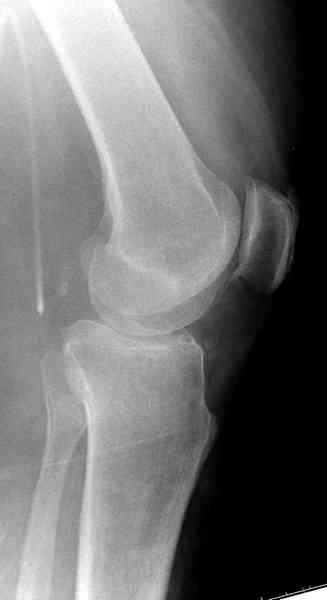

In this situation, where the fragment is posterolateral, one needs a posterior approach, either as described by Timothy Bhatacharya et al in 2005 in JOT, which involves taking down the medial head of the gastrocnemius, or the Lobenhoffer paper which involves a transfibular approach.

would anyone consider an anterolateral approach with a sagital osteotomy just lateral to midline?

this would give access to the impacted posterior region. then "backgraft", and fix the osteotomy

fragment with a standard anterolateral plate. thanks.